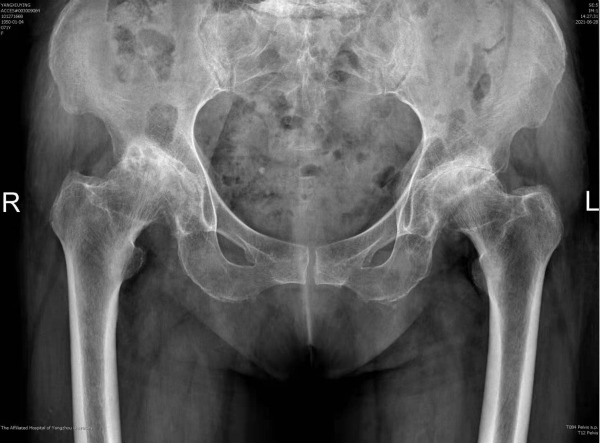

杨女士今年71岁,长年遭受双侧髋部疼痛的困扰,基本丧失行走能力和劳动能力,生活质量受到严重影响。近日,她慕名来到我院骨科就诊,骨科副主任医师徐饶仔细读片后判断杨女士双侧髋关节疼痛的主要原因是双侧髋臼发育不良继发双侧股骨头坏死所致。目前杨女士的双侧股骨头已经磨损变形,关节间隙消失且疼痛明显,已经具备了进行双侧全髋关节置换的指征。